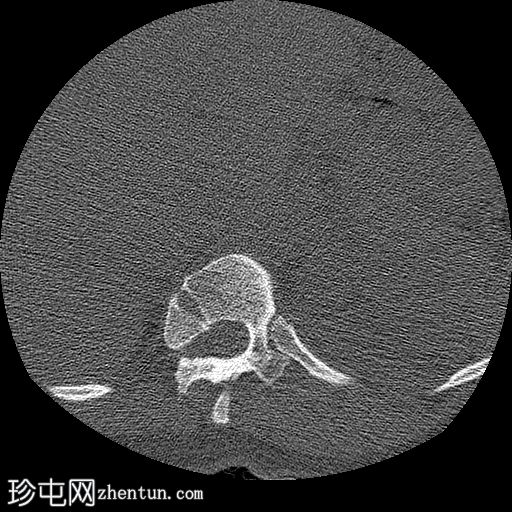

CT

轴位骨窗

胸腰段交界处可见右侧完全节段性半椎体(轴位/矢状位/冠状位)。

未见与上方或下方相邻椎体融合的迹象。